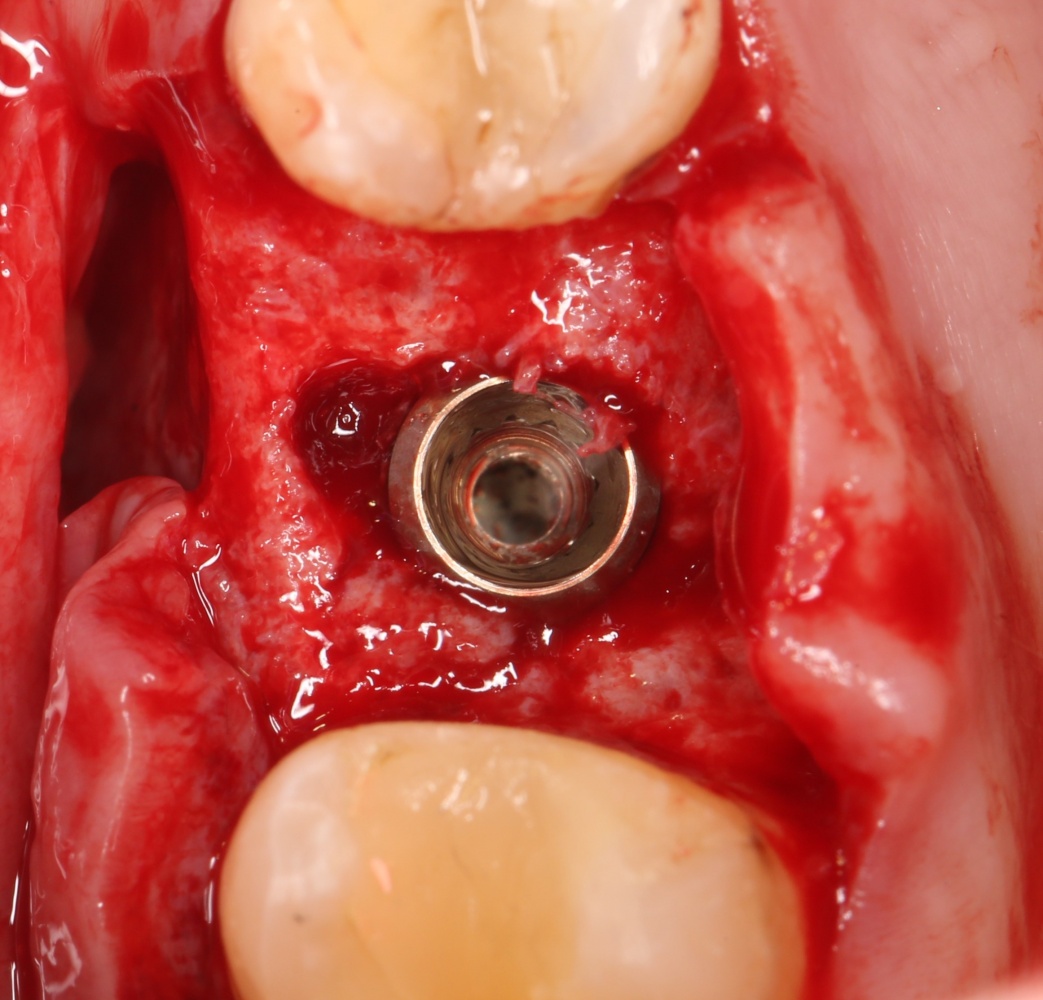

Рекомендации по установке имплантов. Для всех. Часть V.